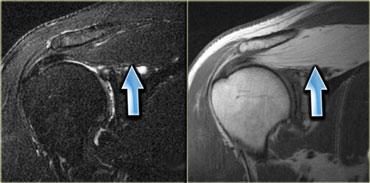

Hình bên trái minh họa một loại cơ phụ thường gặp: cơ dép phụ.

Thông thường, cơ dép bám gần như hoàn toàn vào gân Achilles, với một gân dép nhỏ đi phía trước gân Achilles.

Tuy nhiên, ở khoảng 1-2% dân số, cơ dép đi xuống và bám trực tiếp vào xương gót.

Tình trạng này biểu hiện như một khối có thể sờ thấy và thường, nhưng không phải lúc nào cũng, xuất hiện hai bên.

Hình bên trái cho thấy một cơ dép ở vị trí thấp, nhưng không có điểm bám gân riêng biệt vào xương gót.